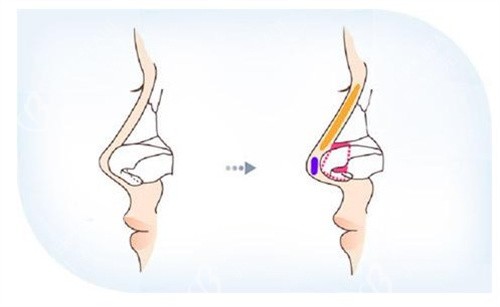

李保锴医生重视鼻部整体力学结构的重建。他提出结构一体化修复概念,强调支撑与自然的统一。这种方式避免传统分段修复的不足,增强鼻部抗外力能力。

他采用肋软骨微雕重塑鼻部支撑,减少再次变形的风险。创新的取肋技术切口小且位置隐蔽,改善后痕迹不明显。动态平衡技术使鼻部触感柔软,仿生结果良好。

对于多次修复失败的鼻子,如挛缩或穿孔情况,他使用复合材料进行重建。结合自体真皮移植和鼻基稳定术,改善功能并延长形态维持时间。